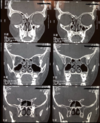

DESCRIBE LA TAC

TAC DE NARIZ Y SPN, CORTE CORONAL NORMAL